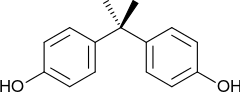

Bisphenol A (BPA) is an organic synthetic compound with the chemical formula (CH3)2C(C6H4OH)2 belonging to the group of diphenylmethane derivatives and bisphenols, with two hydroxyphenyl groups. It is a colorless solid that is soluble in organic solvents, but poorly soluble in water. It has been in commercial use since 1957.

Bisphenol A was first synthesized by the Russian chemist Alexander Dianin in 1891.[14][15] This compound is synthesized by the condensation of acetone (hence the suffix A in the name)[16] with two equivalents of phenol. The reaction is catalyzed by a strong acid, such as hydrochloric acid (HCl) or a sulfonated polystyrene resin. Industrially, a large excess of phenol is used to ensure full condensation; the product mixture of the cumene process (acetone and phenol) may also be used as starting material:[8]

In the early 1930s, the British biochemist Edward Charles Dodds tested BPA as an artificial estrogen, but found it to be 37,000 times less effective than estradiol.[37][38][39] Dodds eventually developed a structurally similar[40] compound, diethylstilbestrol (DES), which was used as a synthetic estrogen drug in women and animals until it was banned due to its risk of causing cancer; the ban on use of DES in humans came in 1971 and in animals, in 1979.[37] BPA was never used as a drug.[37] BPA's ability to mimic the effects of natural estrogen derive from the similarity of phenol groups on both BPA and estradiol, which enable this synthetic molecule to trigger estrogenic pathways in the body.[41] Typically phenol-containing molecules similar to BPA are known to exert weak oestrogenic activities, thus it is also considered an endocrine disrupter (ED) and oestrogenic chemical.[42] Xenoestrogens is another category the chemical BPA fits under because of its capability to interrupt the network that regulates the signals which control the reproductive development in humans and animals.[43]